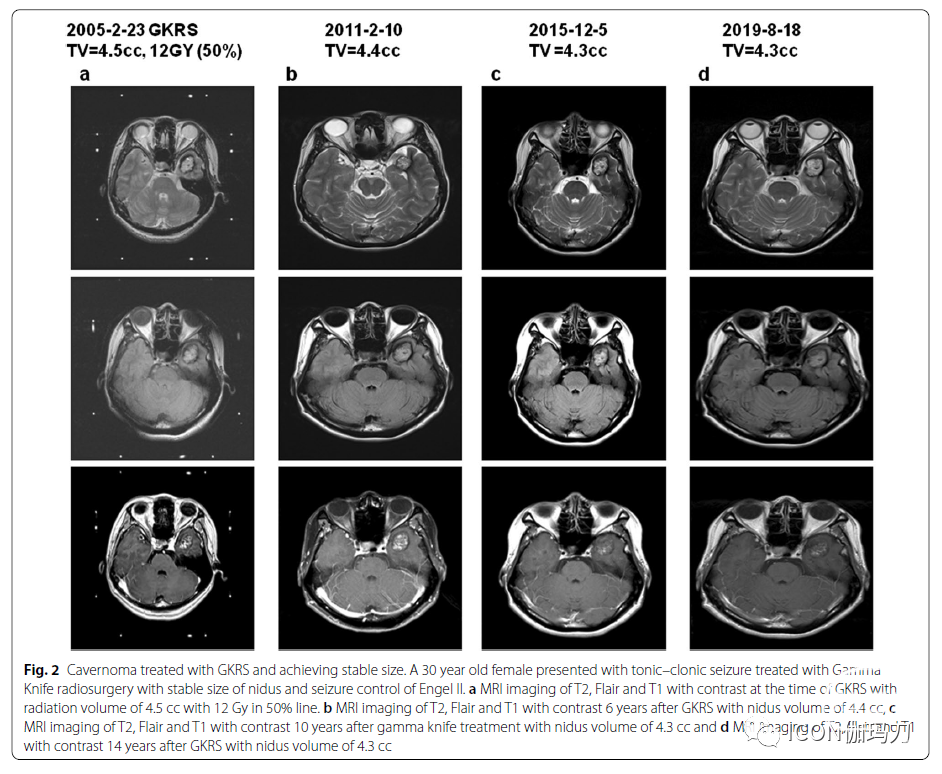

图2经GKRS治疗的海绵状血管瘤大小稳定。一位30岁女性,因强直性阵挛性癫痫发作,接受伽玛刀放射外科治疗,病灶大小稳定,Engel II级癫痫发作控制。GKRS时T2、Flair和T1 MRI,照射体积4.5 cc, 12Gy, 50%线。B GKRS治疗6年后T2,Flair和T1对比增强磁共振成像的病灶体积为4.4 cc, c伽玛刀治疗10年后T2,Flair和T1对比增强磁共振成像的病灶体积为4.3 cc;d GKRS治疗 14年后T2,Flair和T1对比增强磁共振成像上病灶体积4.3 cc。